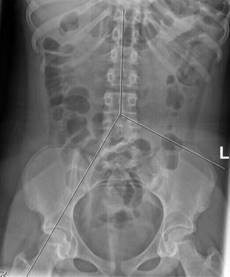

Para determinar el subtipo de estreñimiento funcional se estableció el sitio donde se encontraban al menos dos de los 10 marcadores radiopacos (zona positiva). Para establecer el sitio anatómico de los marcadores se trazaron tres líneas sobre la radiografía abdominal: una vertical sobre las apófisis espinosas de las últimas vértebras torácicas hasta la quinta lumbar (L5), otra oblicua desde el cuerpo vertebral de L5 hasta la parte superior del fémur derecho, y una tercera línea horizontal, del borde superior de la vértebra L5 hasta la espina iliaca anterosuperior izquierda (Figura 2).

Figura 2: Radiografía de abdomen que muestra los segmentos colónicos. Delimitadas las áreas del colon: colon derecho e izquierdo en la parte superior y sigmoides en la parte inferior. Se considera positivo dos o más marcadores en cada área.

Las tres líneas delimitaron tres áreas: el colon derecho entre las líneas 1 y 2; el colon izquierdo entre las líneas 1 y 3, y el recto sigmoides por debajo de las líneas 2 y 3. Si los marcadores se encontraron en el colon se consideró un estreñimiento por “inercia colónica”; en la zona del sigmoides como asociado con “alteración del piso pélvico”. En caso de que los marcadores se identificaran en más de una zona se consideró como causa mixta, y cuando se determinó la ausencia de marcadores, el diagnóstico fue de “estreñimiento funcional o de tránsito normal”.